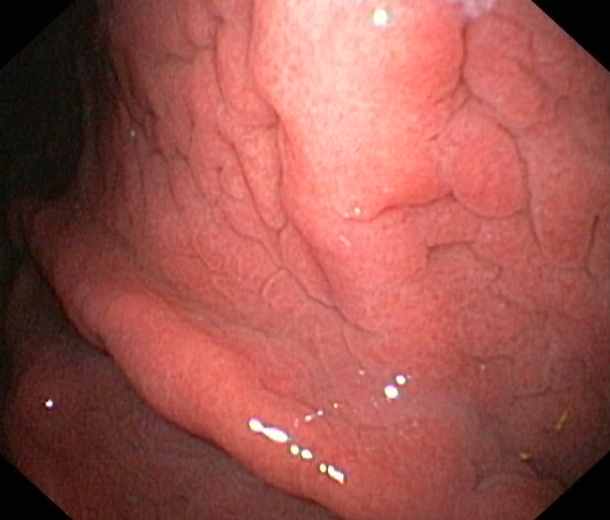

Gastritis caused by a chronic Helicobacter Pylori-infektion